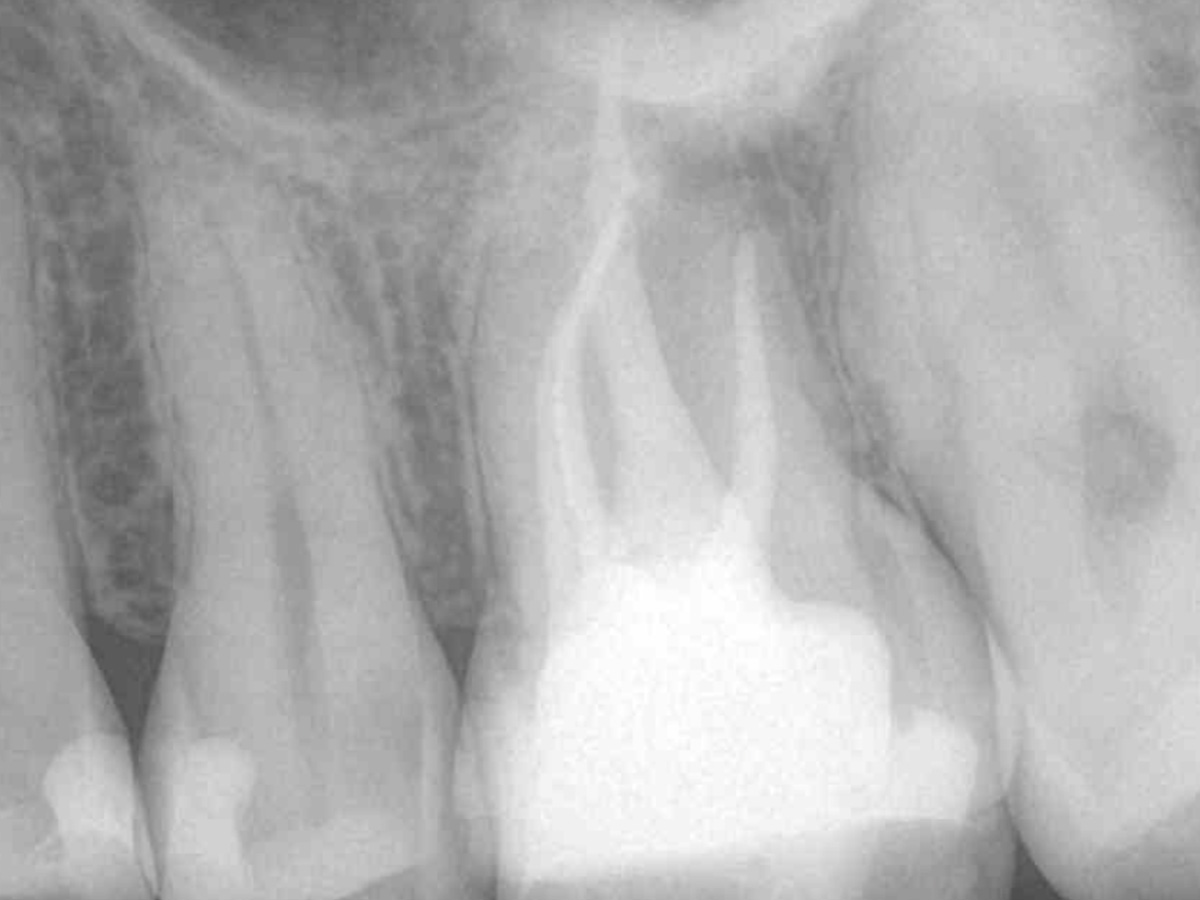

Mit dem B&L Beta wurde der restliche Kanal nach der Backfill-Technik schrittweise mit erwärmter Guttapercha aufgefüllt. Die abschließenden Röntgenaufnahmen zeigen das Ergebnis, das mit den kabellosen Systemen präzise und effizient umgesetzt werden konnte.

Abbildung 4

Abbildung 5

Abbildung 6

Wurzelfüllung 26 exzentrisch

Abbildung 7

Wurzelfüllung 26 orthoadial